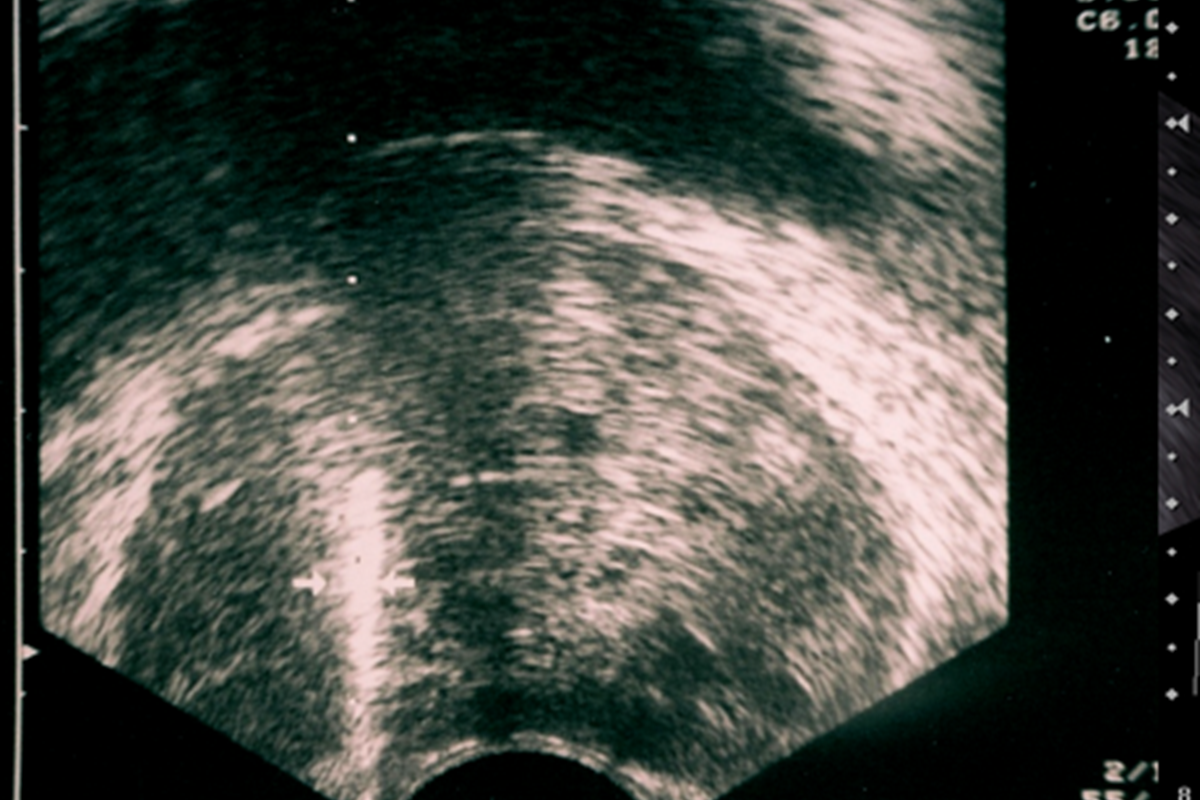

Transrektal ultrason eşliğinde prostat biyopsisi öncesinde, hasta yukarıda belirtildiği şekilde hazırlanır. İşlem lokal anestezi ile yapıldığından, hastanın aç olmasına gerek yoktur. Lavman ile makat temizliği yapıldıktan sonra, hasta sedye üzerine, sol yan tarafına doğru dönerek yatar ve dizlerini karnına doğru çeker. Hastanın üzeri örtüldükten sonra, iç çamaşırı aşağıya sıyrılır. Doktor, kaydırıcı ve uyuşturucu özellikleri olan bir jeli hastanın makat bölgesine sürer. Daha sonra, prob adı verilen ince ultrason başlığını yavaş bir şekilde hastanın makat bölgesine yerleştirir. Bu, tüm prostat biyopsisi işleminin en önemli aşamalarından biridir. Doktor makat bölgesini aniden zorlamamalı, başlığı içeriye yavaş yavaş, hastanın canını yakmadan yerleştirmelidir. Hastamız kendisini gevşek bırakır ve makat bölgesini sıkmazsa, başlık hiç rahatsızlık vermeden, yumuşak bir şekilde içeri doğru ilerler. Kendisini sıkan hastalarda bile, zorlama yapılmadan yavaş davranılırsa, makat girişi bir süre sonra gevşeyerek başlığın acısız bir şekilde girmesine izin vermektedir. Çok nadiren (yaklaşık %1), makat girişinde darlık ya da yarası olan hastalarda bu aşamada şiddetli ağrı olabilir. Bu durumda hastanın canını acıtarak işleme devam etmeyiz. İşlem hasta uyutularak, anestezi altında yapılır.

Başlığı makat bölgesine yerleştirdikten sonra, Ultrason’da prostat çok net olarak görülür. Önce, çok ince bir iğneyle prostat çevresine uyuşturucu ilaç verilir. Böylece prostat uyuşur ve işlemin bundan sonraki kısmını hasta sadece sinek ısırığı gibi hafif bir acı olarak hisseder. Ultrason ile prostat görülürken, özel bir iğne ile prostatın içinden parçalar alınır. TRUS prostat biyopsisinde, genellikle prostattan 12 adet parça alınmaktadır. PSA’sı çok yüksek olan hastalarda bu sayı azalırken, prostatı çok büyük olan hastalarda, tekrar biyopsilerde veya şüpheli odak görülen biyopsilerde alınan parça sayısı 14-18’lere kadar çıkabilir. İşlem yaklaşık 15 dakika kadar sürer ve yukarıda da bahsettiğimiz gibi, hastamız çok az ağrı hissederek işlemi tamamlar.